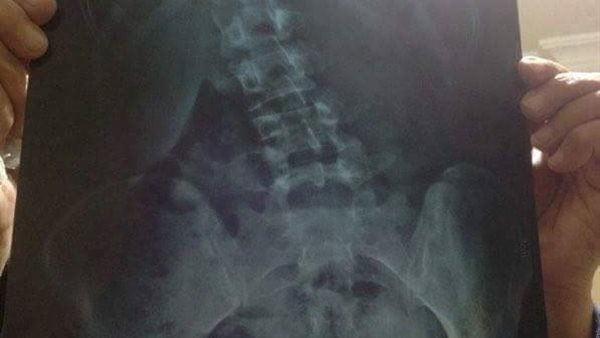

كثرة الكتب فى المناهج المصرية كان لها تأثير كبير على بعض التلاميذ خاصة فى شنطة المدرسة والتى يحملها ابنائنا على ظهورهم، حيث أثرت إحدى الشنط المدرسية على طالبة، وعمودها الفقرى، والتى لم تستطيع تحمل هذه الآلم أثناء أدائها الامتحان، والمقدر بثلاثة ساعات، وينشر موقع السبورة صورة أشعة العمود الفقرى لهذه الطالبة ومدى تأثير حقيبة المدرسة عليها، حتى أصبح ابناؤنا ينطبق عليهم الاية القرآنية الكريمة "مثل الحمار يحمل أسفارا"...

دي صوره اشعه توضح اثار شنطه المدرسه علي العمود الفقري لطالبه....والتي اكتشفت المشكله اثناء اداءها للامتحان الذي كانت مدته ثلاث ساعات لم تستطع البنت ان تكملها جالسه في الامتحان من شده الالم..... كلامي ليس من وحي الخيال... ولكن اسال عليه يوم القيامه.